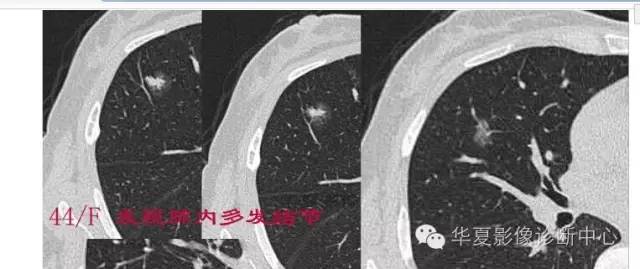

周围GGO边界清楚,分叶征、胸膜凹陷征、含气支气管,混合型GGO

两个病灶

第一步:判断是否GGO

第二步:判断是否肿瘤

第三步:看边缘及内部征象

磨玻璃结节良恶性影像分析策略 混合型,边界清楚、分叶征,考虑肺癌